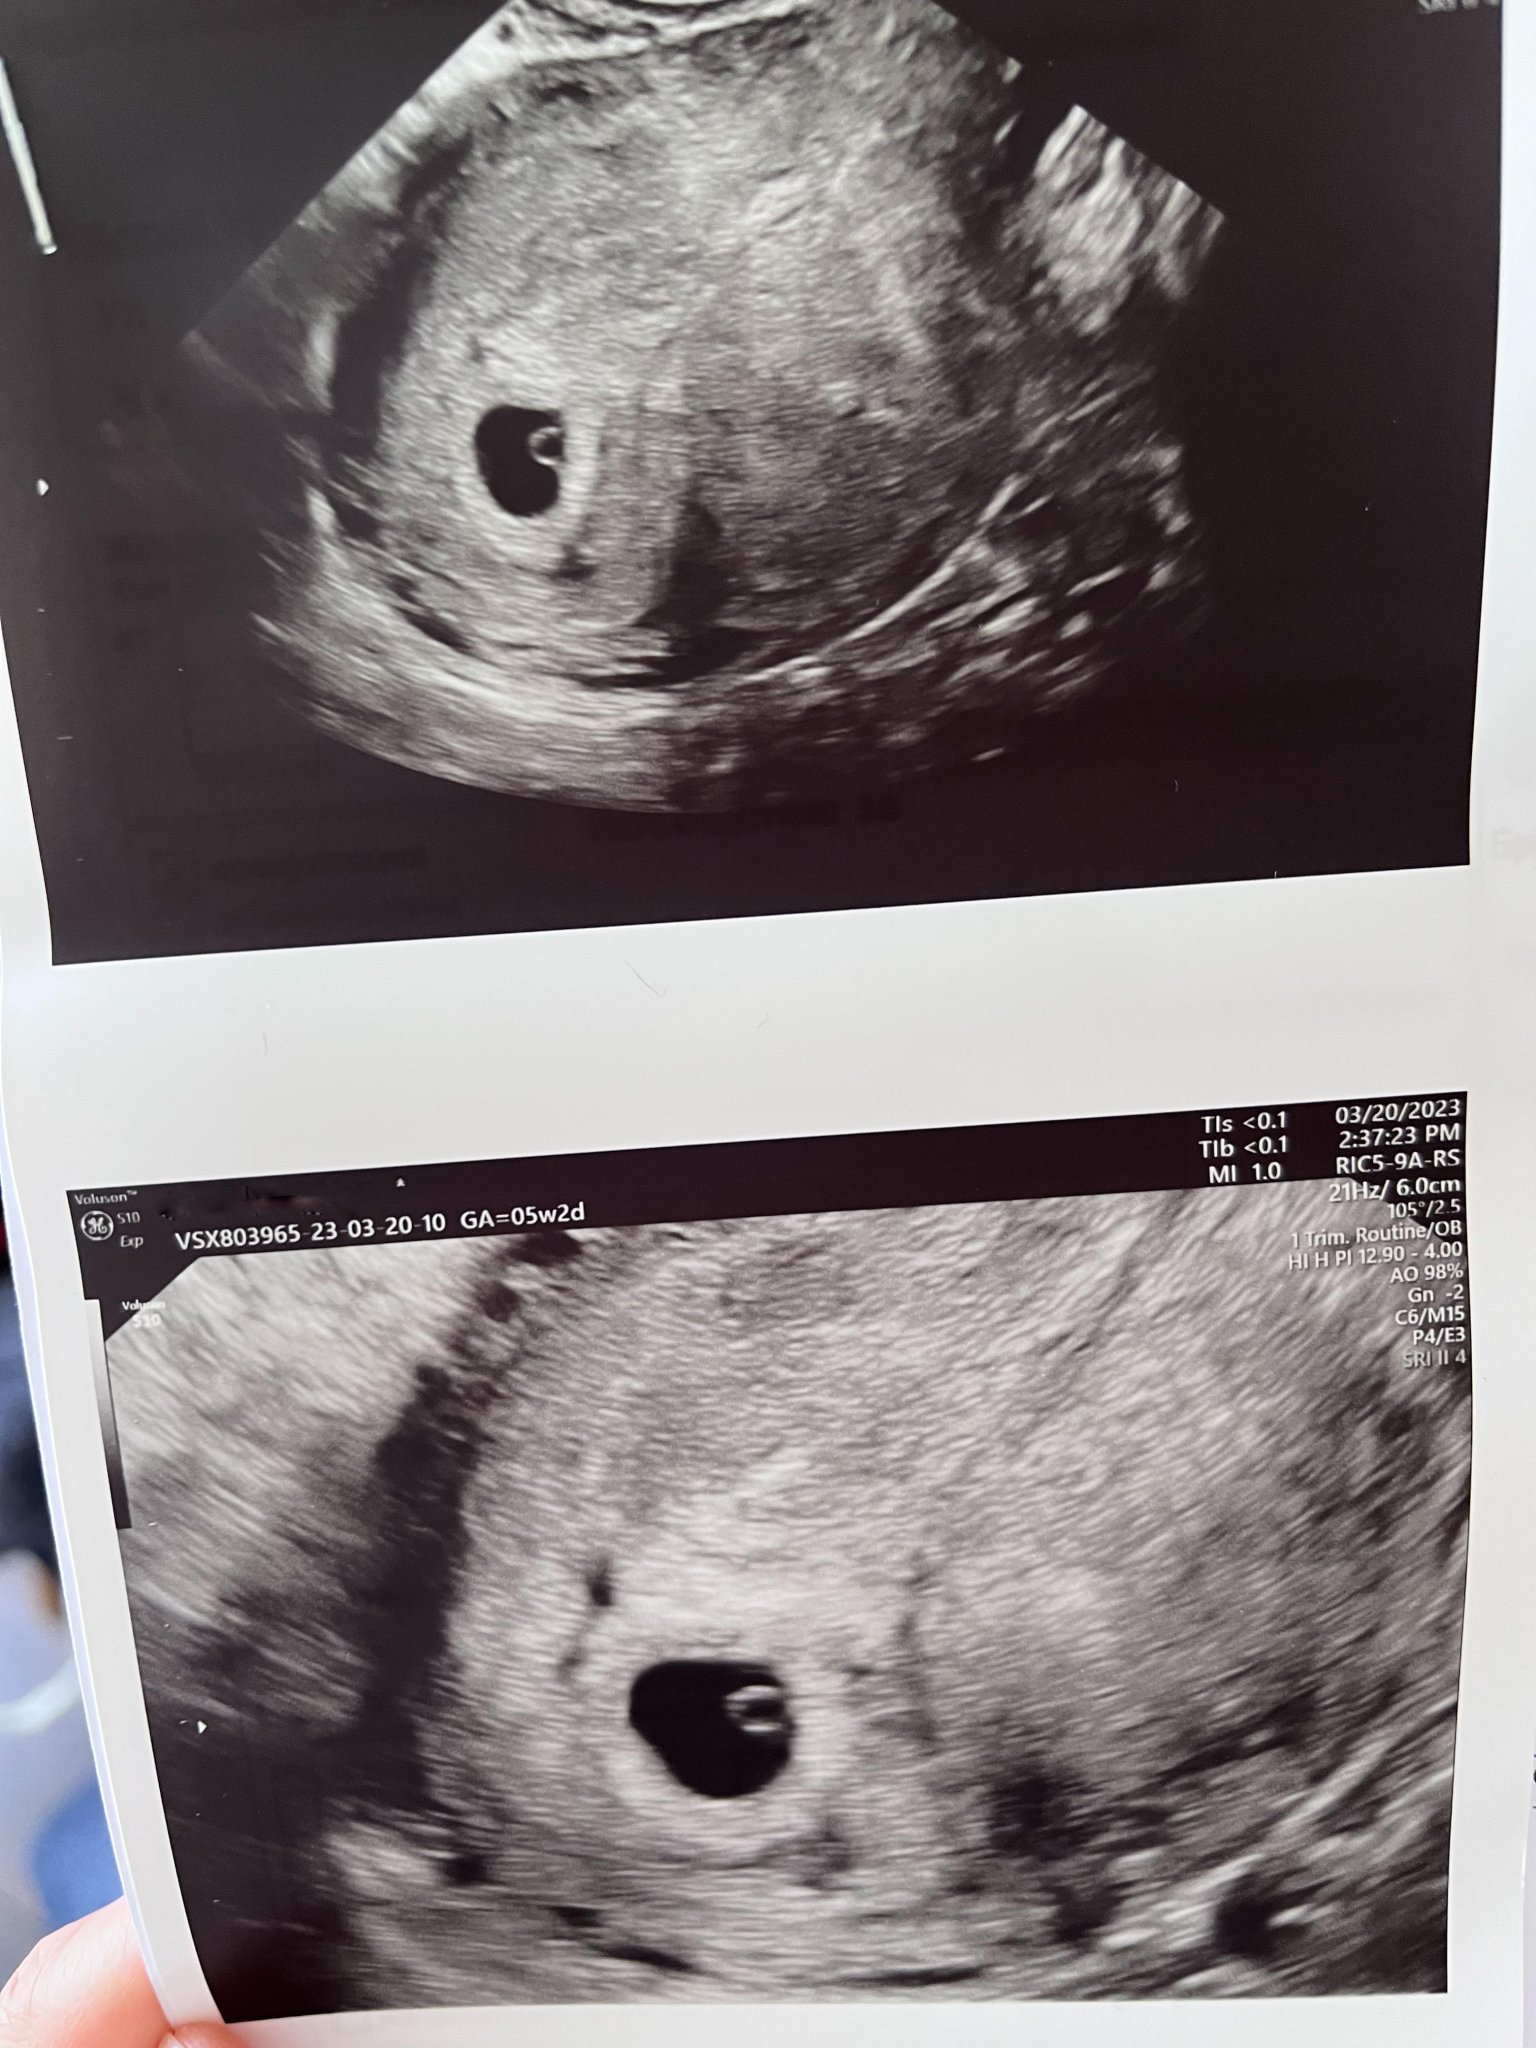

Момичета, бях на преглед и според снимката от ехографа съм 5 седмица + 2 дни. Последен цикъл 11.02. Обаче в приложението на телефона ми излиза, че съм 6-та и вече трябвало да има ембрион и сърдечна дейност. На прегледа обаче се видя само сак 9мм и ми казаха да ида другата седмица да се види ембрион и сърдечна дейност и аз нещо се филмирах естествено. Питах си АГто нормално ли е това, което вижда, за този етап - каза "да", но в мен остана това тъпо чувство, че нещо не е в ред. Сега, в коя седмица съм реално и на този етап време ли е да се е видял ембрион и сърдечна дейност, или е рано? Прикачам снимка, ако някой нещо разбира.

Скрит текст:

5+2 е 6г.с. Информацията, която ти дава приложението е за завършена 6г.с. така че не се притеснявай. Има време да се види Simple Smile